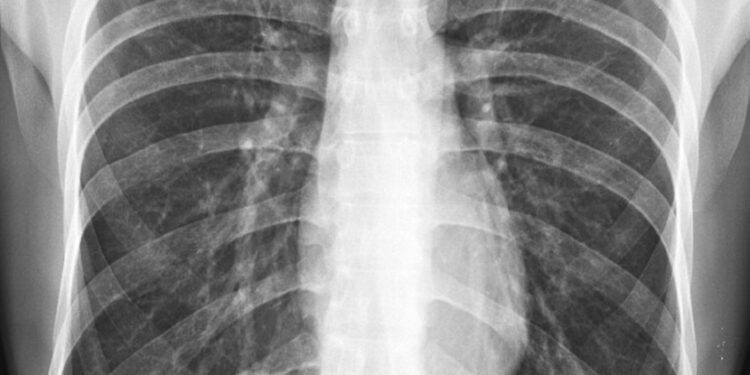

Aptikus mekonijų vaisiaus vandenyse, medicinos personalas ypatingai stebi naujagimį po gimimo, ieškodami kvėpavimo sutrikimų požymių. Norint įvertinti padėtį, gali būti atliekama auskultacija (klausomasi kvėpavimo garsų) ir krūtinės ląstos rentgenograma. Tyrimai padeda tiksliai įvertinti, ar mekonijus pateko į plaučius ir ar yra uždegimo ar skysčių sankaupų.

- Krūtinės rentgenograma – rodo uždegiminius pokyčius ar skysčius plaučiuose